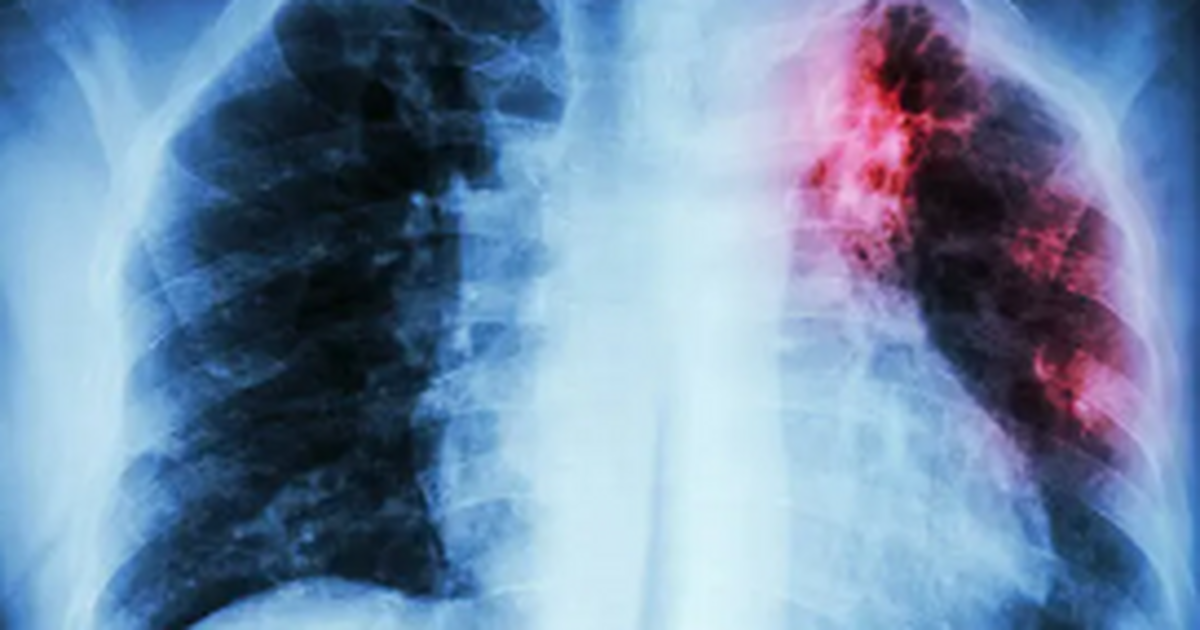

По словам биолога Юлии Кривошеевой, туберкулёз — это хроническое инфекционное заболевание, которое нередко протекает бессимптомно. Его возбудителем является микобактерия туберкулёза, или палочка Коха, способная длительное время сохраняться во внешней среде. Она может поражать практически все органы и системы организма, но чаще всего страдают лёгкие.